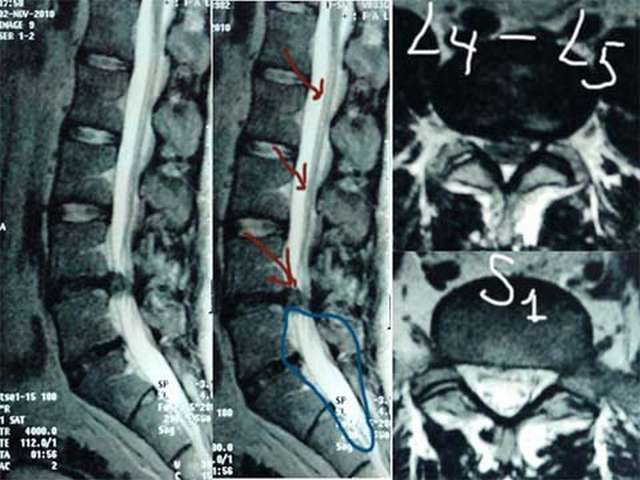

Выполнена МРТ поясничного отдела позвоночника: выявлена парамедианная грыжа диска L4-L5 0,9х0,4 см. Кроме того, специалистами МРТ выявлены признаки врожденного синдрома натянутого спинного мозга (tethered cord syndrome): спинной мозг прослеживается до уровня S2 позвонка и заканчивается в липоме, окружающей концевую нить на уровне S3, дистальные отделы дурального мешка расширены, конус спинного мозга имеет атипичную вытянутую форму.